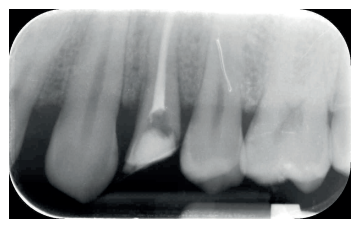

Las revisiones se realizaron de forma periódica hasta los 12 meses de seguimiento (Figuras 6 y 7), observando en todas ellas signos clínicos saludables. El paciente no presentó reabsorción radicular, anquilosis, ni problema periodontal en los exámenes radiográficos que se realizaron desde el diagnóstico hasta el año (Figuras 8 -12); y la ganancia de ferrule obtenida de 2mm se mantuvo estable.

de seguimiento al año de la extrusión.

seguimiento al año de la extrusión.

momento de la endodoncia.

momento de la rehabilitación.

de las citas de seguimiento.